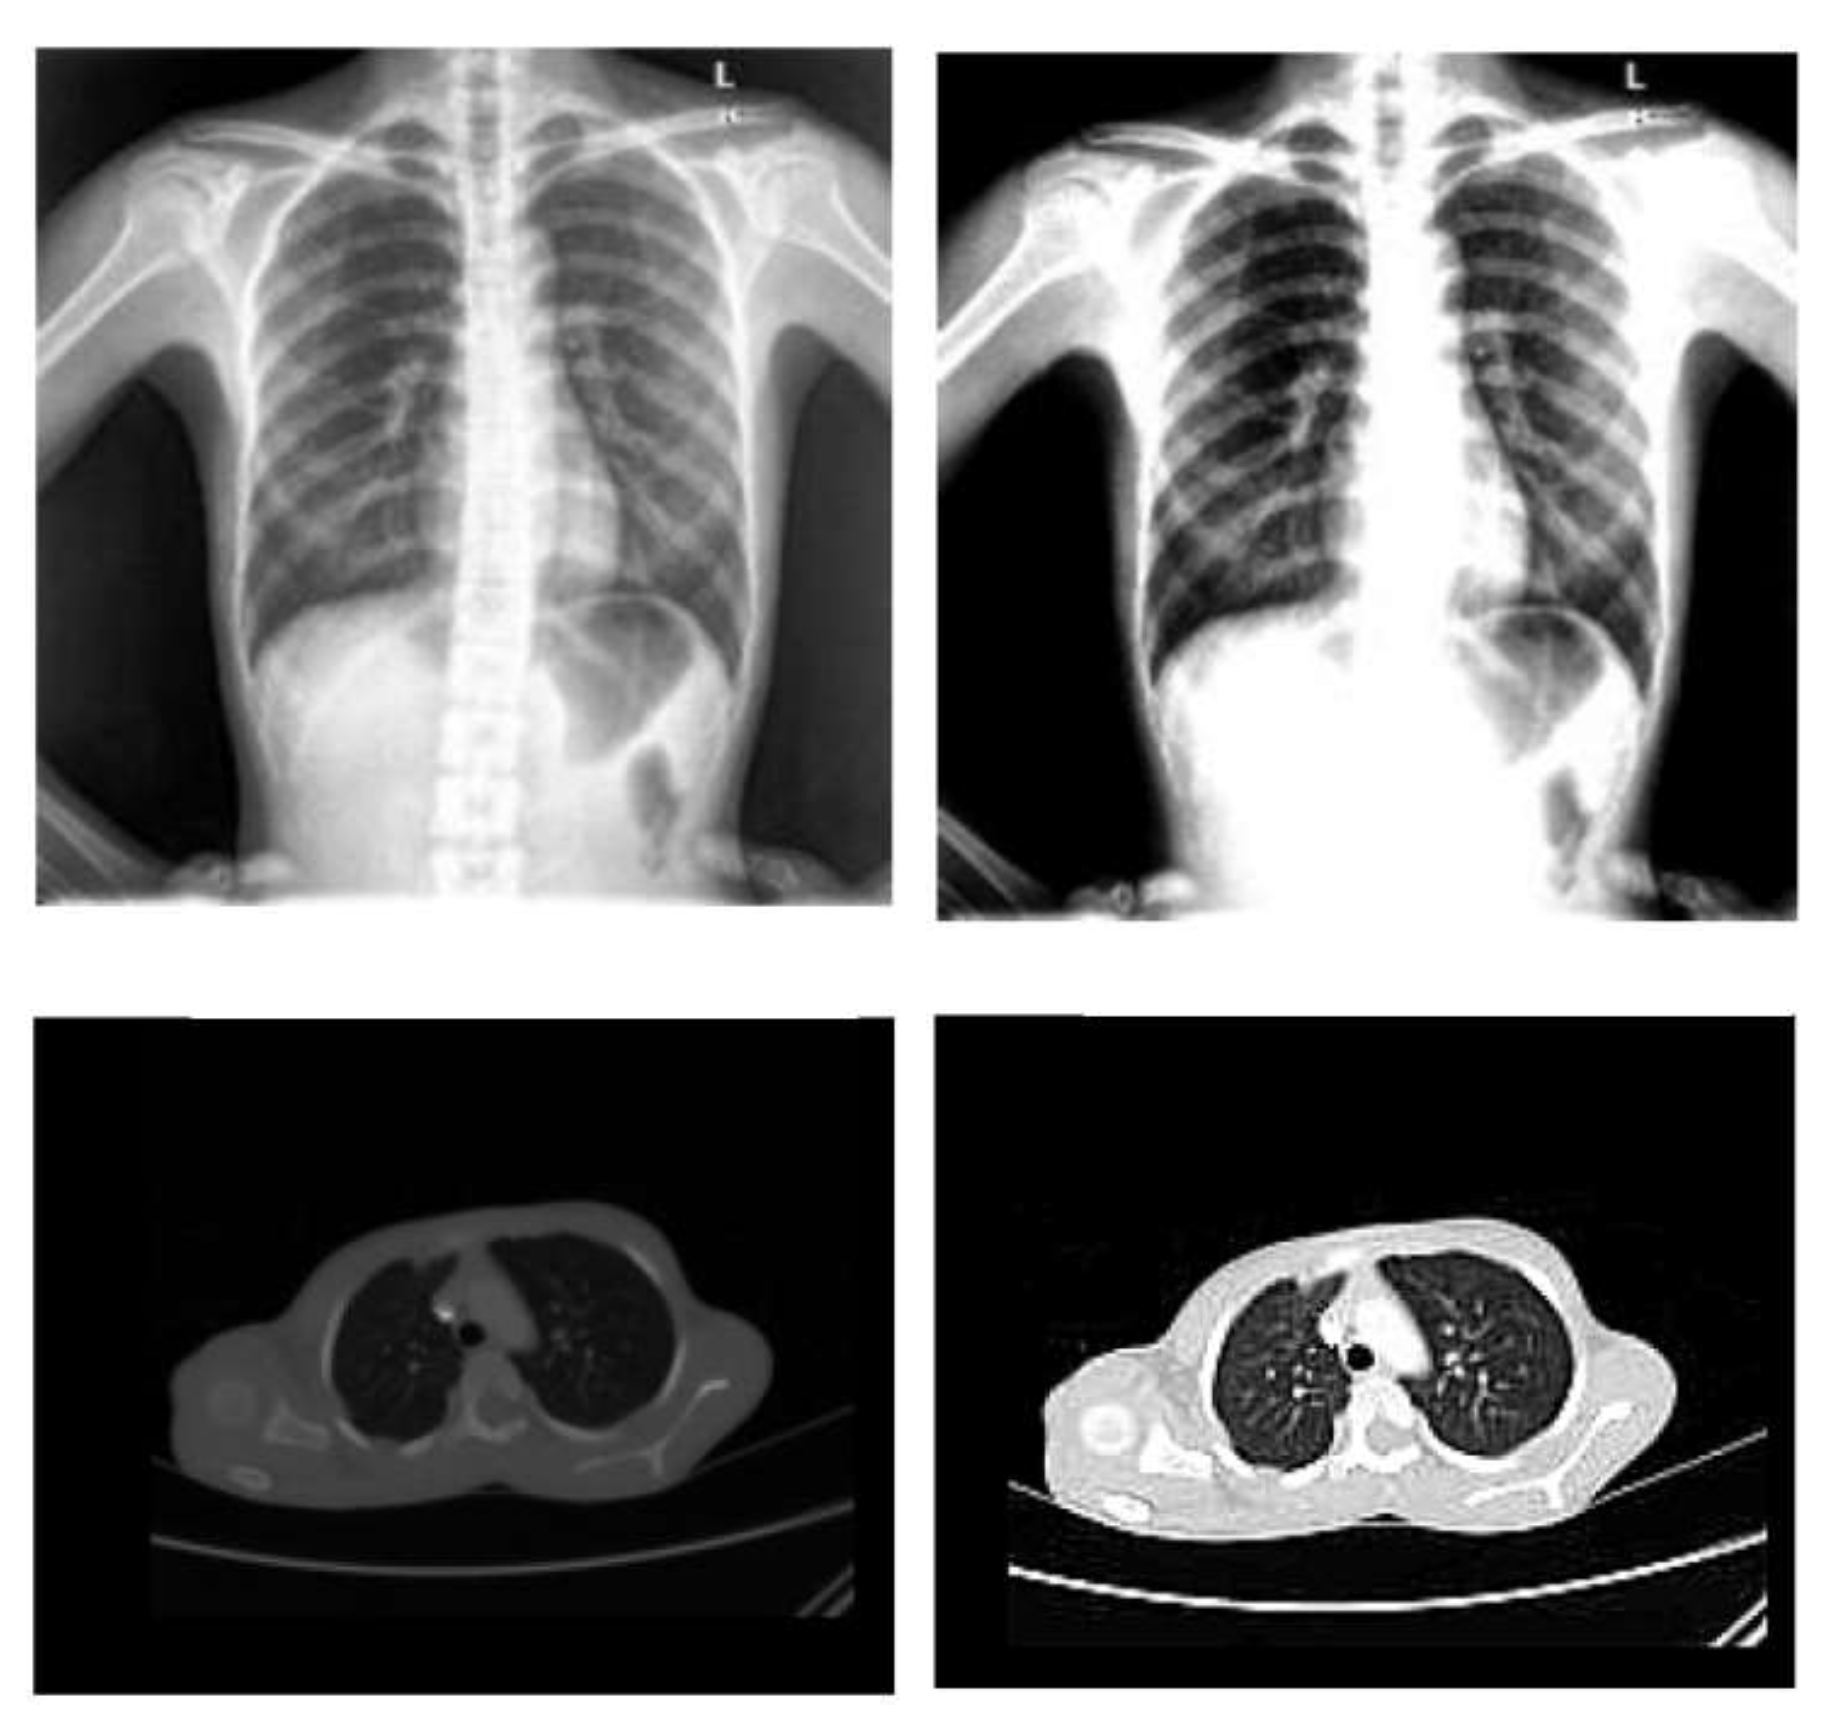

- Normalization: To improve the convergence of the training phase, input pixels to any AI system must have a normalized data distribution. To normalize an image, the distribution’s mean value is first subtracted from each pixel, then divided by the result by the standard deviation. Sample X-ray and CT images are shown in Figure 2 before (on the left) and after (on the right) the preprocessing steps.